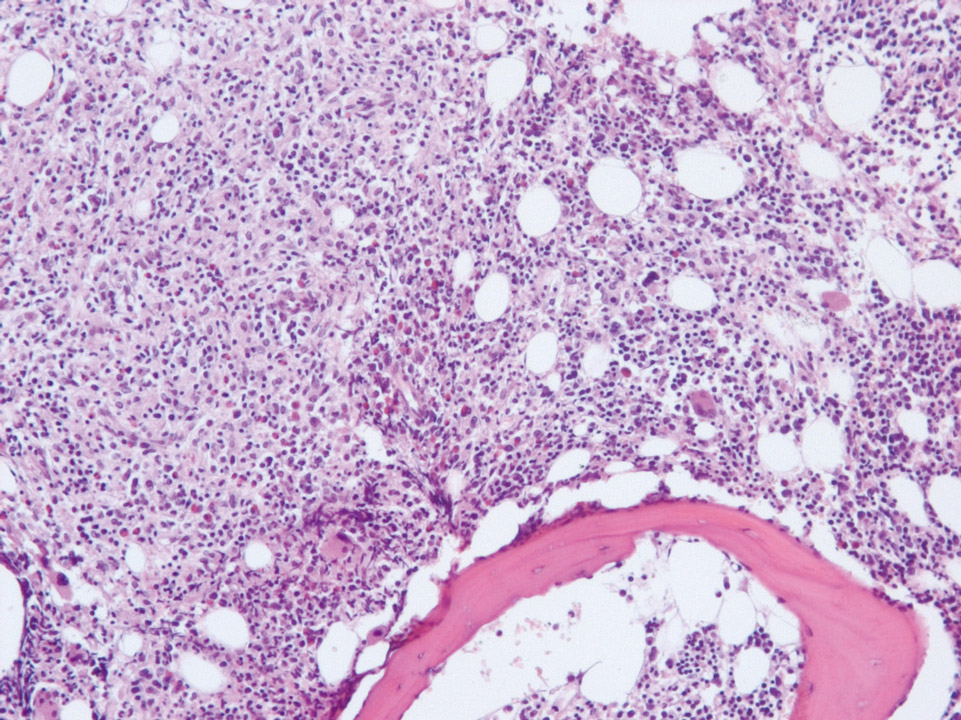

Микропрепараты: Лимфогранулематоз и Нодулярный Склероз